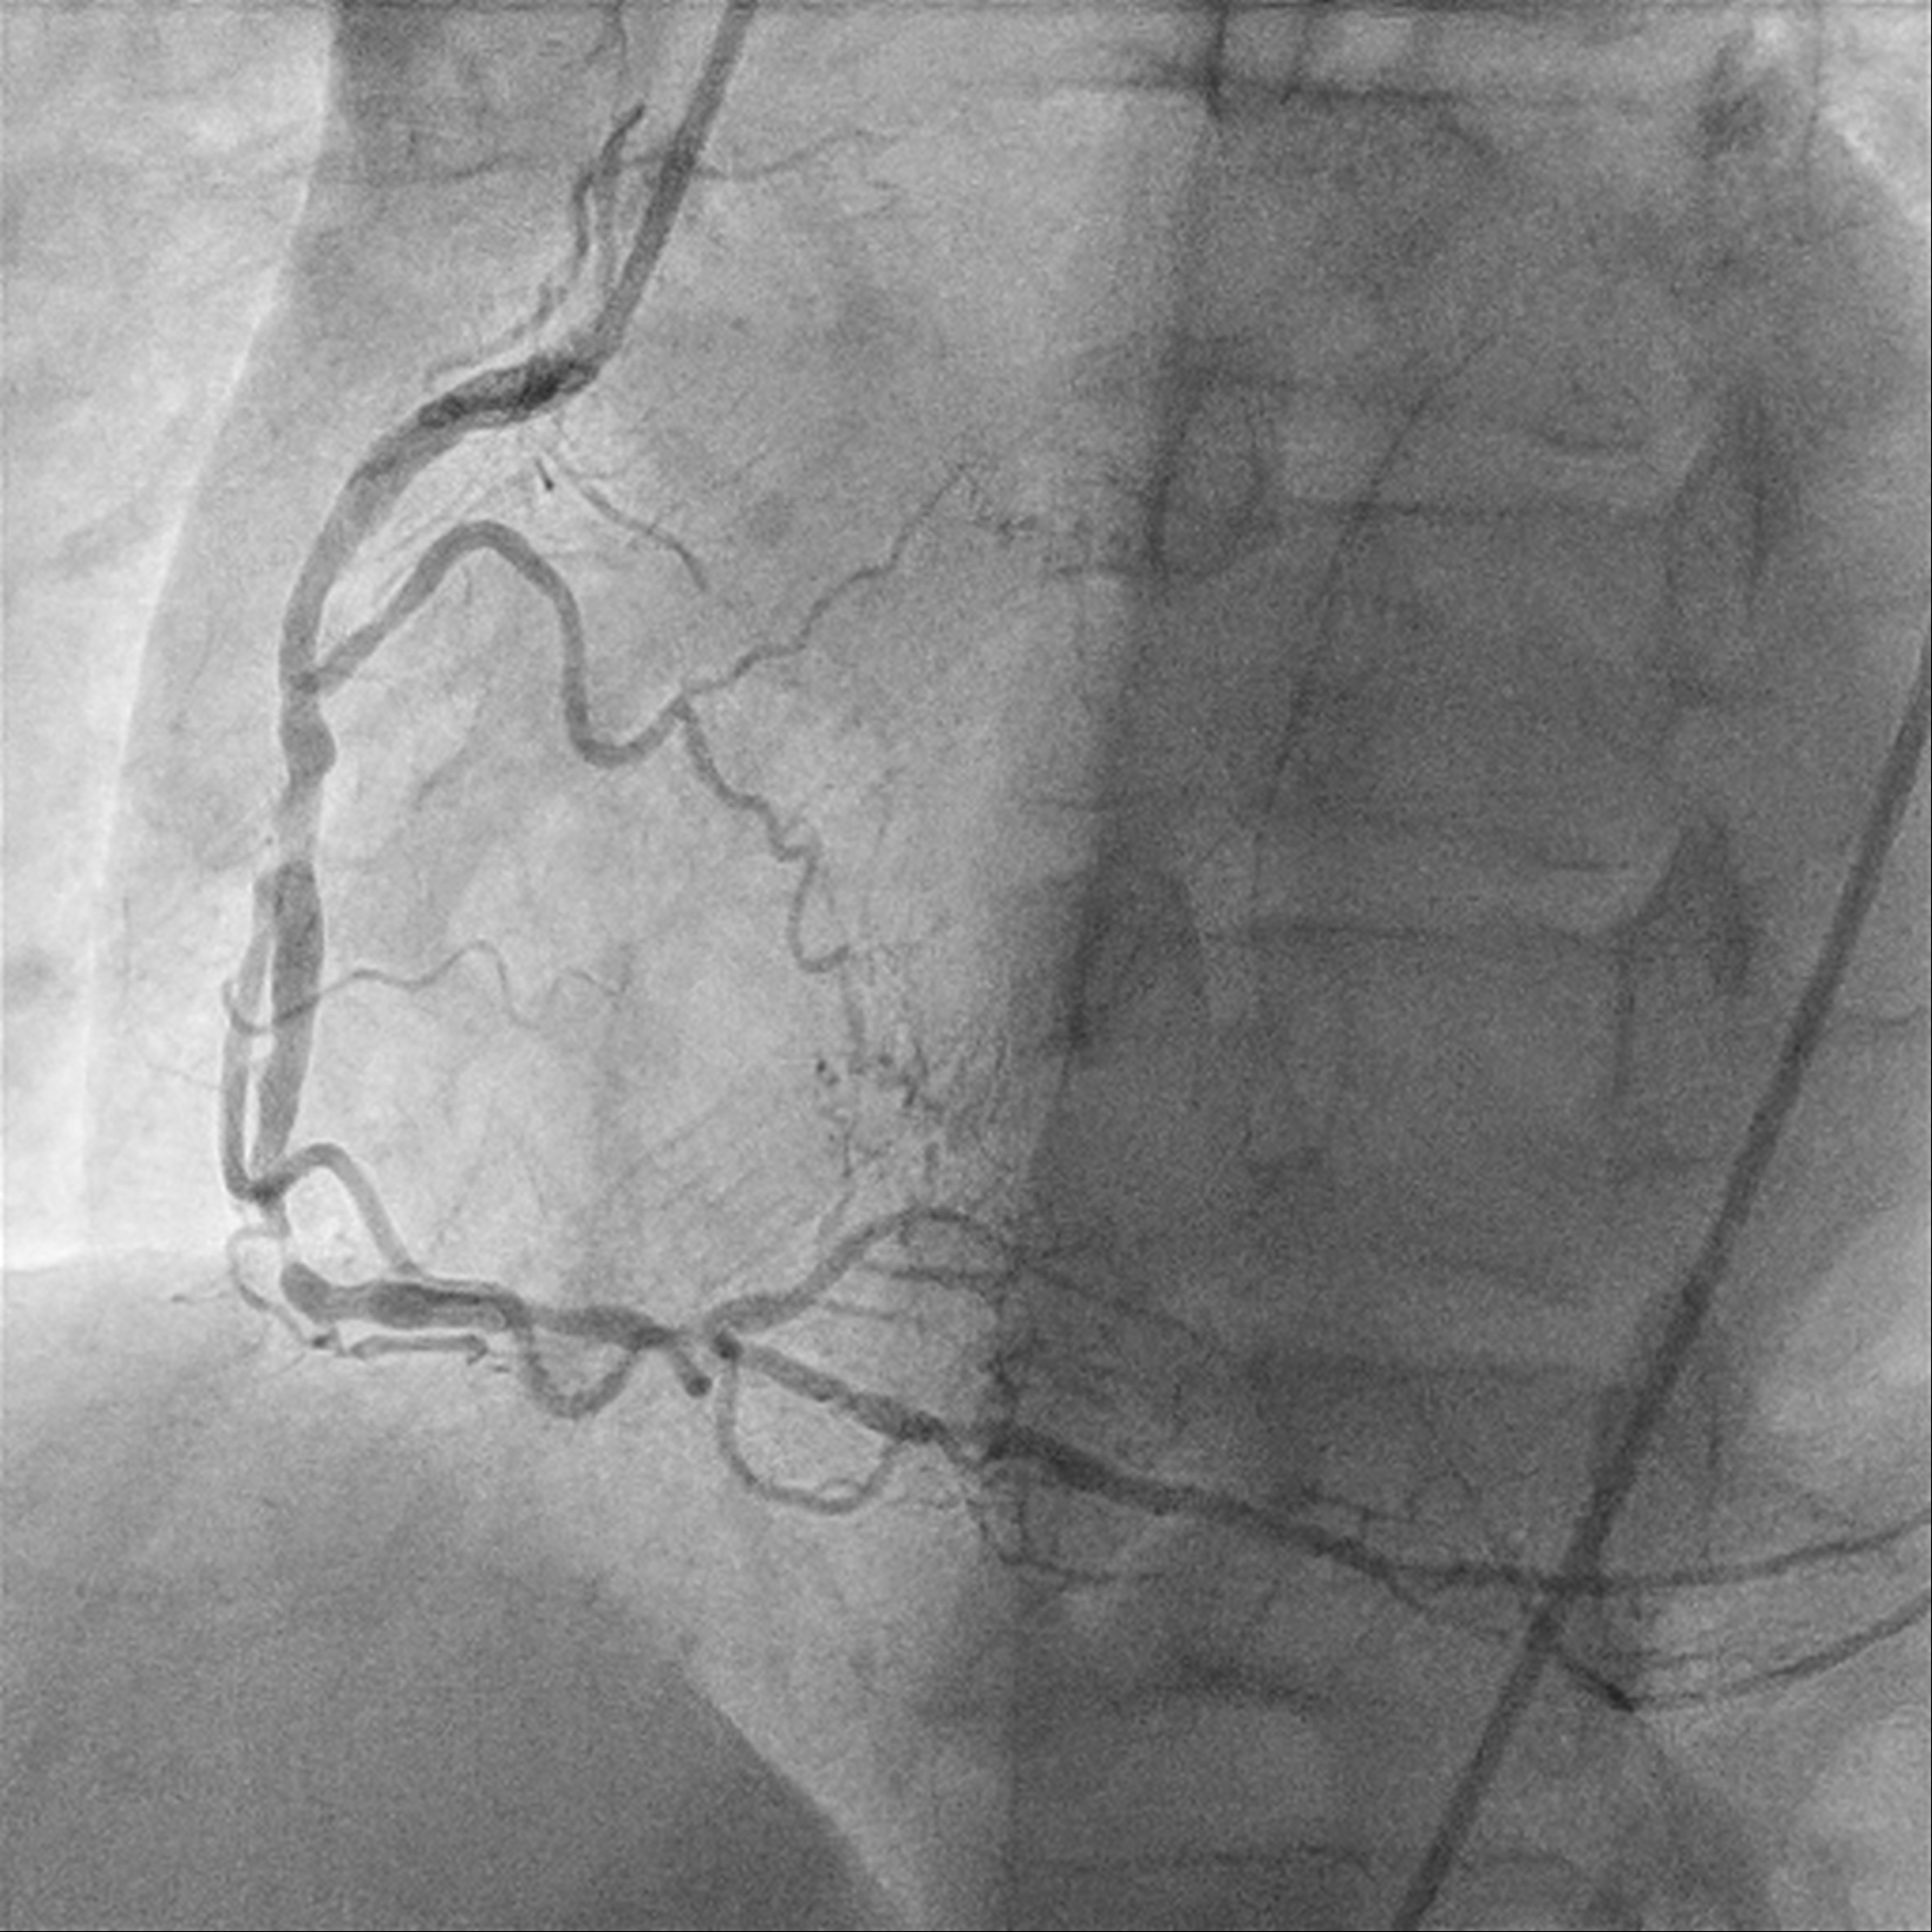

A 49-year-old male who is a chronic smoker and ex-IV drug addict was presented as heart failure and NSTEMI. Severely impaired LV systolic function of 15%, global hypokinesia. Calcified coronary arteries with mRCA severe stenosis, mid to distal RCA critical lesion; retrograde flow from PL branch to mLAD. mLAD CTO with bridging collaterals. LCX diffuse moderate stenosis, with collateral to PL branch. MRI heart confirms viable myocardial over LAD territory, CABG turned down.

Relevant Catheterization Findings